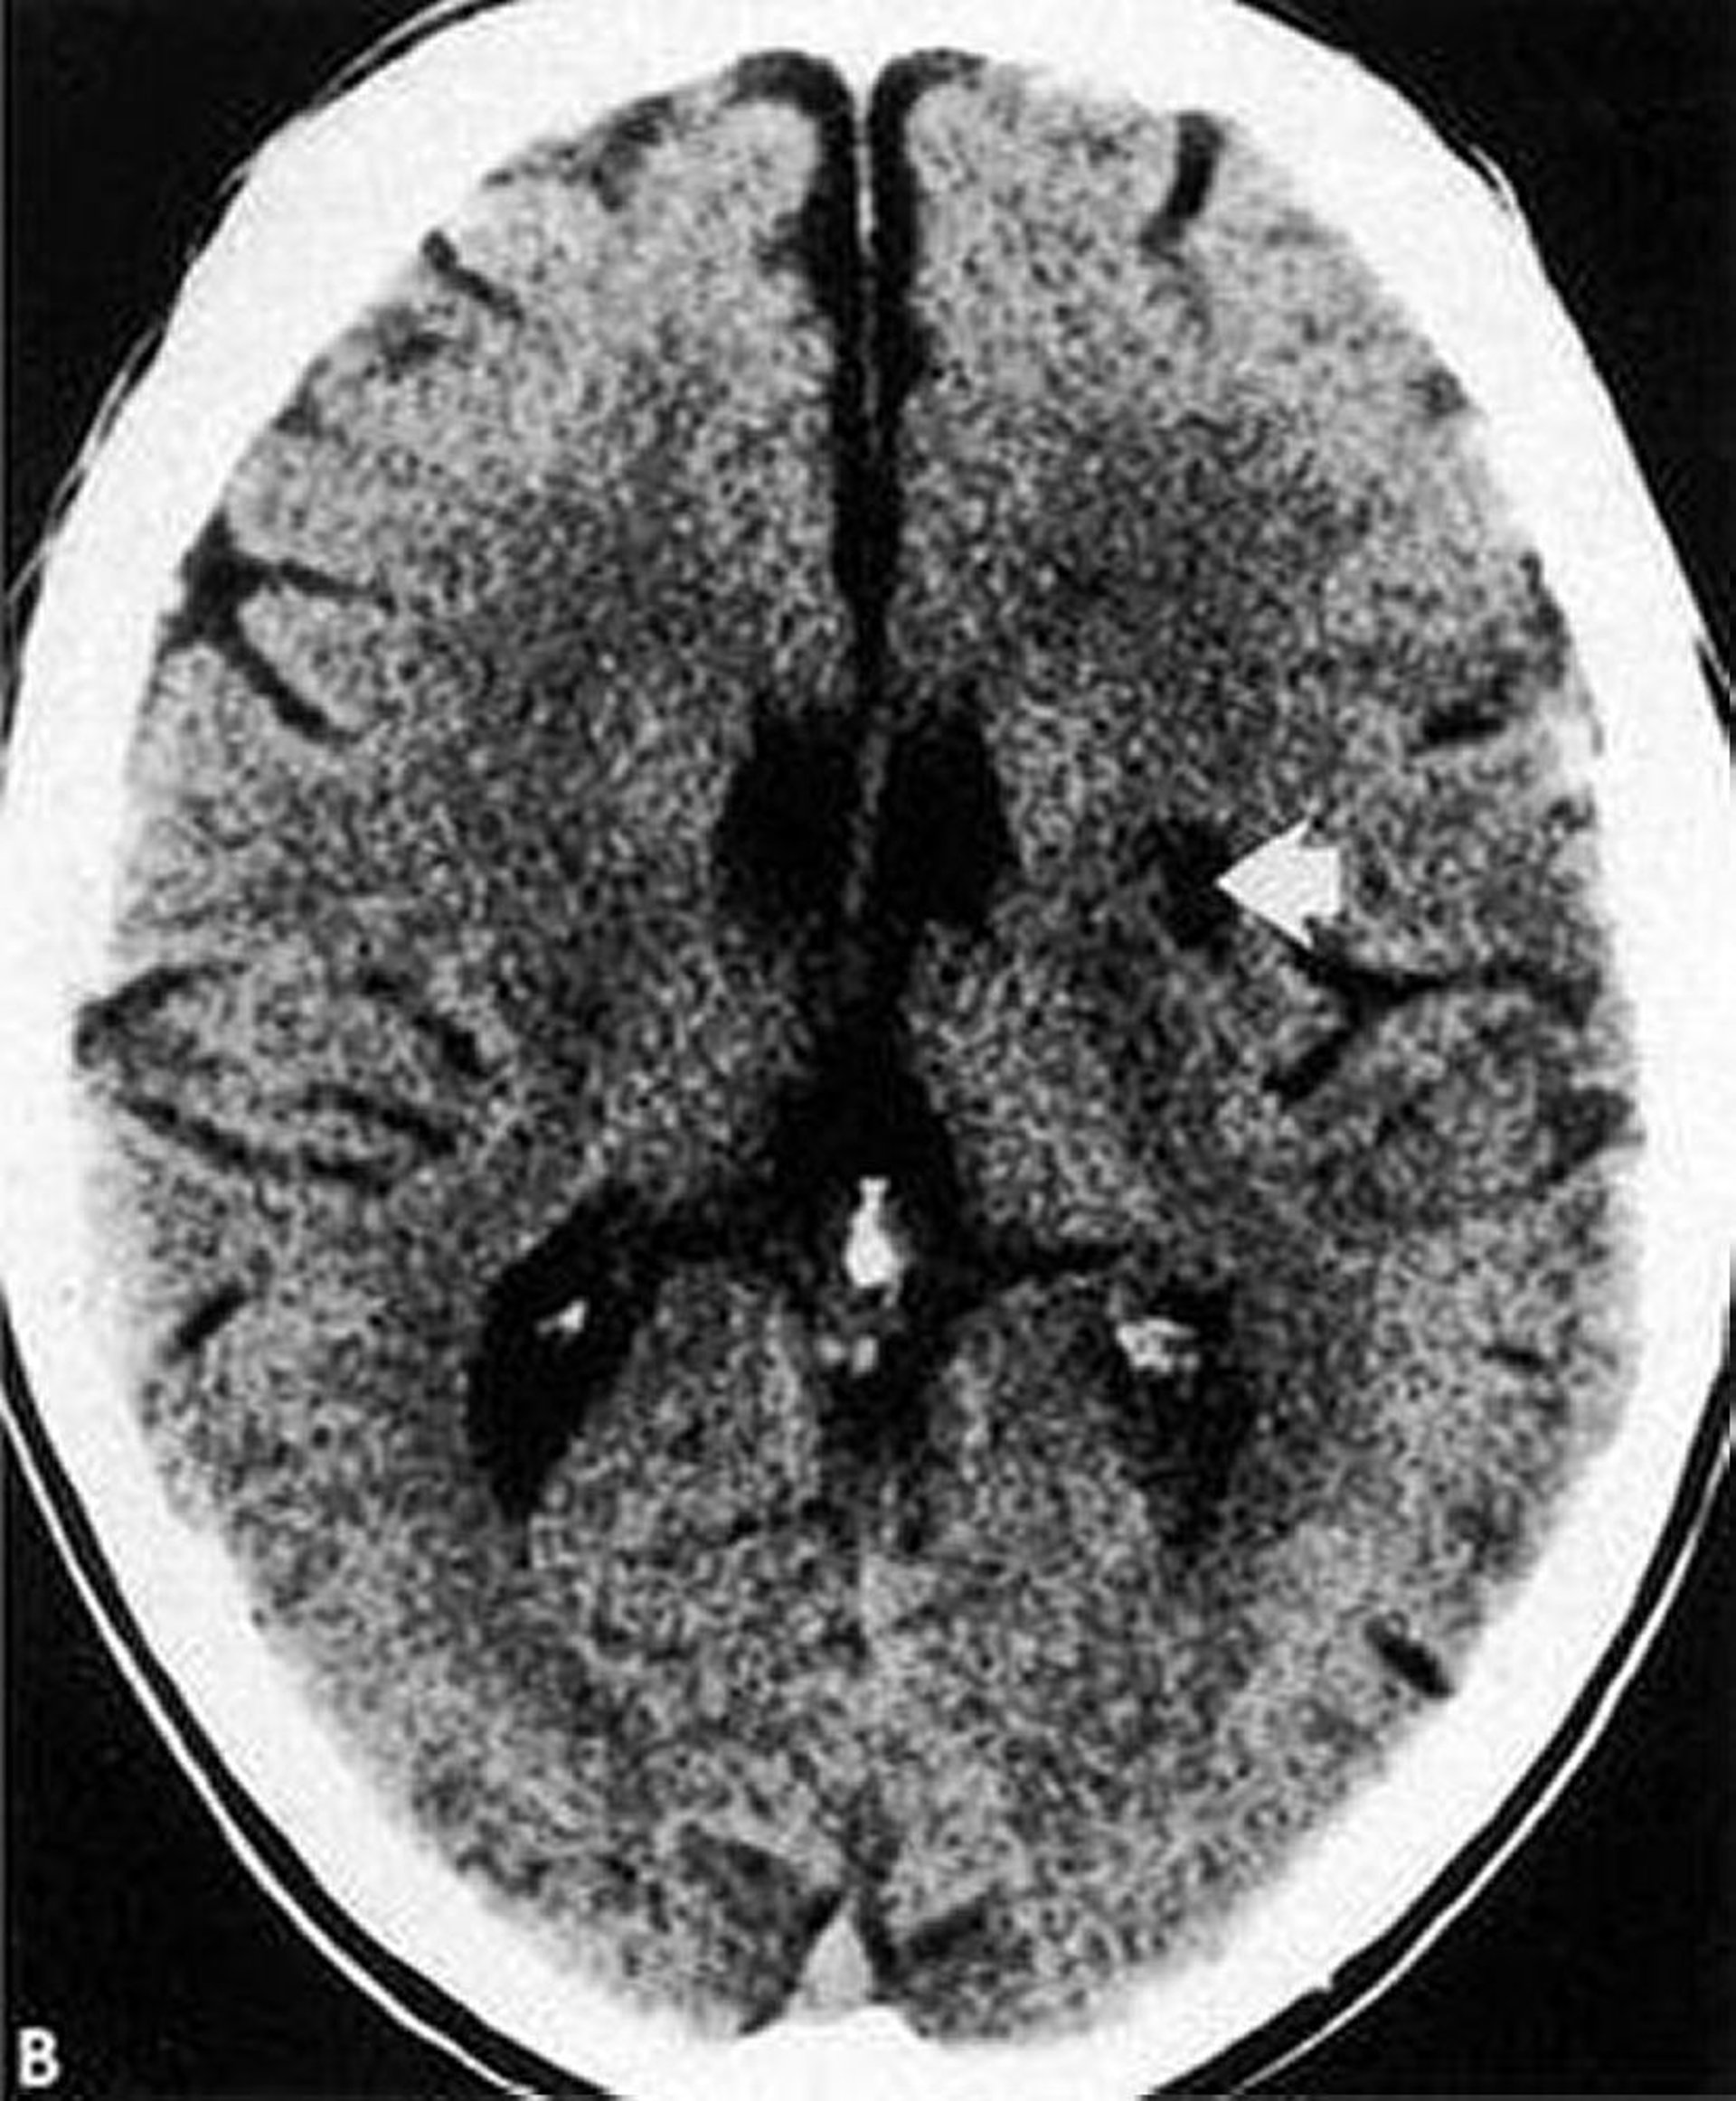

This CT scan shows a low-density, well-defined lacunar infarct (arrow) within the basal ganglia.

By permission of the publisher. From Geremia G, Greenlee W. In Atlas of Cerebrovascular Disease. Edited by PB Gorelick and MA Sloan. Philadelphia, Current Medicine, 1996.